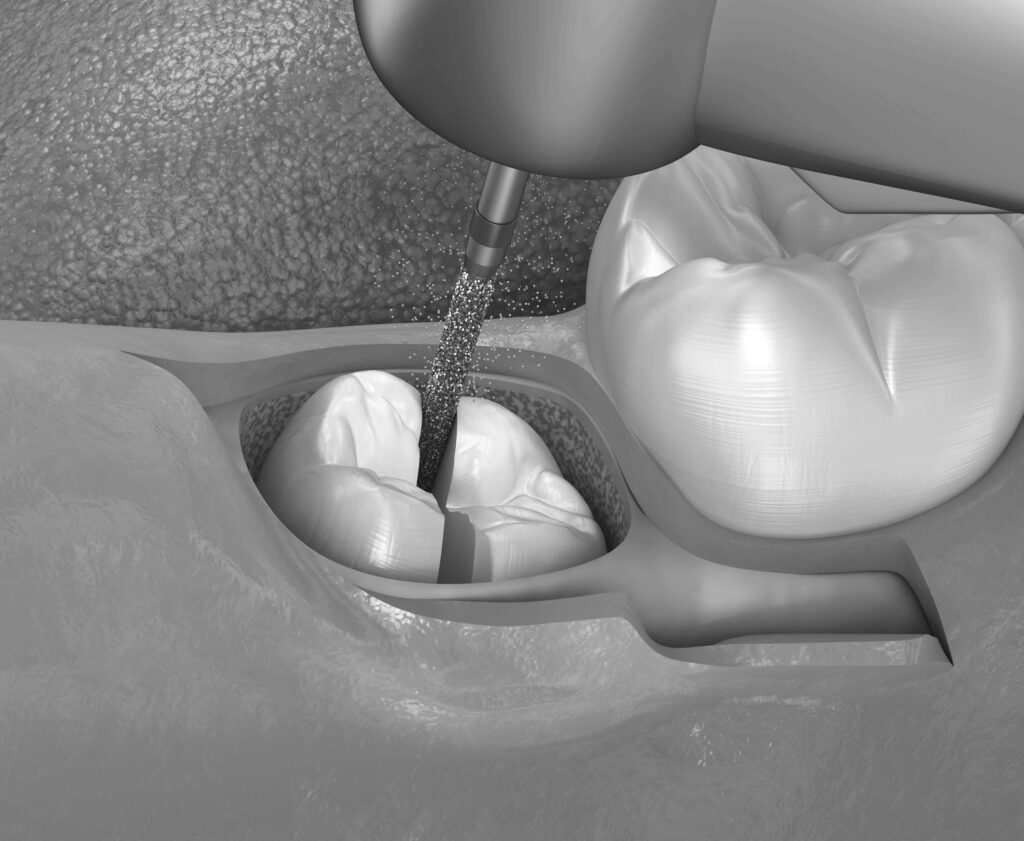

특히 매복된 사랑니는 부분적으로만 잇몸 밖으로 나오는 경우가 많아 이를 제대로 관리하지 않으면 주변 치아에까지 영향을 줄 수 있습니다. 이런 경우 발치를 하는 것이 가장 적절한 방법입니다.

하지만 사랑니 발치는 사랑니의 위치와 형태에 따라 발치의 난이도가 달라질 수 있습니다.

수평으로 누운 사랑니는 발치 과정에서 잇몸과 턱뼈에 심한 압력을 가할 수 있어 통증과 부작용이 따를 수 있지만 영도치과 수도치과에서는 철저한 사전 진단과 계획을 통해 이러한 문제를 줄여줍니다.